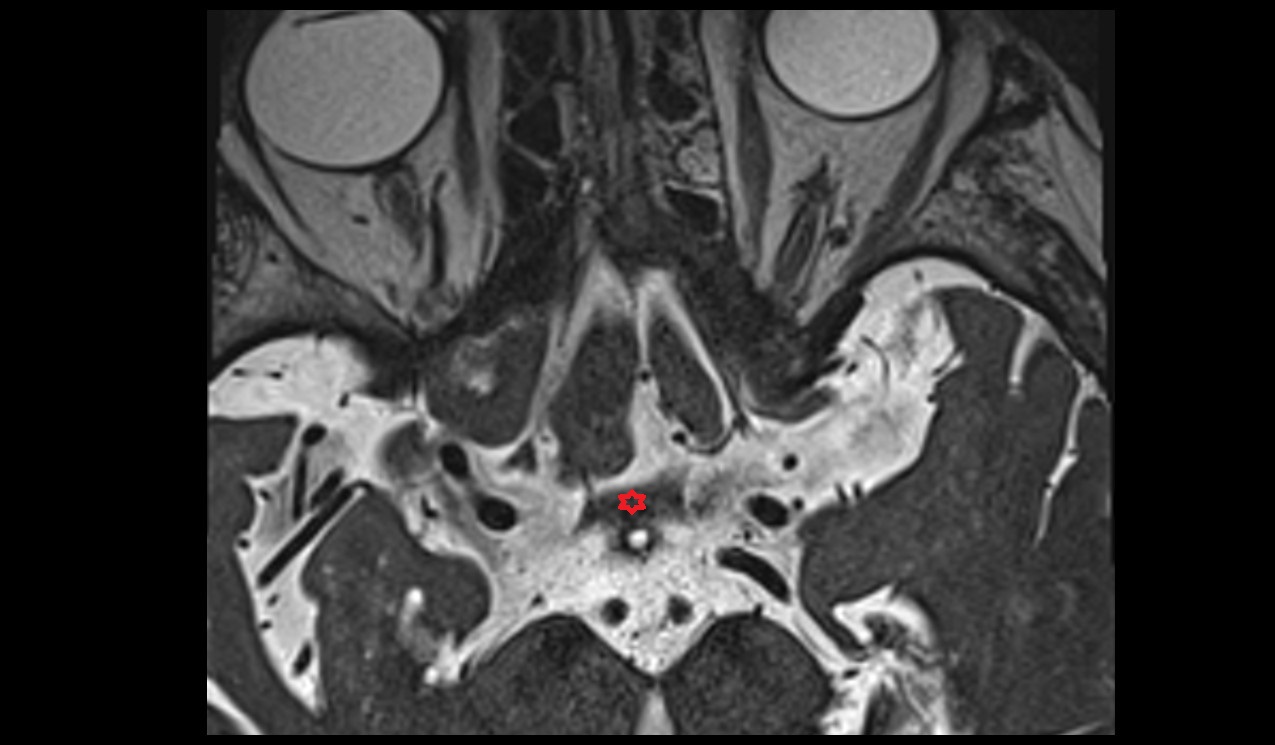

- Peripheral zone of prostate

- Anterior Fibromuscular Stroma of prostate

- Central zone of prostate

- Transitional zone of prostate